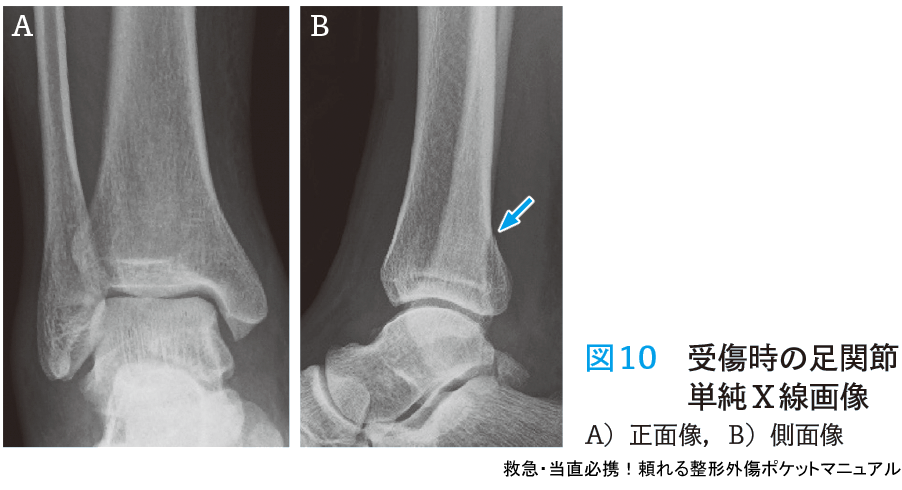

- 所見と経過:右足関節に腫脹があり,同部位の疼痛と圧痛もあった.単純X線では脛骨遠位部骨折(後果骨折)があったため(図10)下腿シーネ固定を行い,後日整形外科外来受診を指示した.荷重制限については指示しておらず,帰宅後は患肢荷重を行っていた.6日後に整形外科外来を受診したが,右足関節骨折および腓骨近位部骨折の診断となり(図11),緊急で創外固定手術を行った.

- 単純X線検査では患側4方向(正面・側面・両斜位)および健側2方向(正面・側面)撮影を行う.

- 脛骨遠位部骨折があり腓骨遠位部骨折がない場合や,腓骨骨幹部に圧痛を伴う場合,患側下腿2方向(正面・側面)を追加し骨折の有無を確認する.